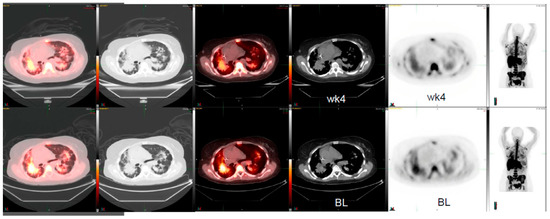

Patient 1: The first patient in the case study is a 49-year-old male with small cell lung cancer who received cisplatin and etoposide as standard therapy. After progression from standard therapy, the patient was placed on a c-MET inhibitor therapy. We compared conventional CT, FLT-PET/CT, and FDG-PET/CT scans pre- and post-four weeks of targeted therapy (Figure 1). In this patient, the pre-therapy tumor CT measurements were 1.5 cm × 0.7 cm, which remained unchanged post therapy after four weeks. While the 18F-FDG PET/CT showed a 2% increase in SUVmax from 1.64 to 1.67, 18F-FLT PET/CT showed a reduction in metabolic activity of 38% from 1.3 to 0.8 SUVmax (Figure 1).

Patient 2: This is a 51-year-old female with a history of relapsed and refractory lung adenocarcinoma. This patient received several lines of therapy that included erlotinib, carboplatin, gemcitabine/docetaxel, pemetrexed, sorafenib, irinotecan, and then bevacizumab. After progression on standard therapy, the patient was enrolled in a c-MET inhibitor-targeted-therapy clinical trial. At that time, she presented with a right hilar mass (Figure 2). The two-dimensional CT tumor measurements were 5.2 cm × 4.6 cm and post therapy were 5.3 cm × 4.8 cm. The change corresponds to a 2% increase in tumor size. However, the 18F-FLT PET/CT imaging pre- and post-therapy after four weeks revealed a SUVmax of 5.1 and 3.9, respectively, which was a 24% reduction in 18F-FLT activity. Although not significant statistically, it was a clinically significant response to therapy.

Figure 1. 3′-deoxy-3′[(18)F]-fluorothymidine (18F-FLT) positron emission tomography/computed tomography (PET/CT) scans shows early response to c-MET inhibitor targeted therapy whereas the conventional CT scan and 2-deoxy-2-[18F]-fluoro-D-glucose (18F-FDG) PET/CT images do not show any responses in this patient with small cell lung cancer (BL, baseline; wk4, at 4 weeks post therapy).Arrows show the location of tumors.